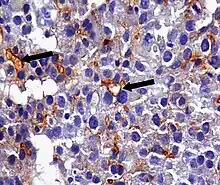

An anti-CEA antibody is an antibody against CEA. Such antibodies to CEA are commonly used in immunohistochemistry to identify cells expressing the glycoprotein in tissue samples. In adults, CEA is primarily expressed in cells of tumors (some malignant, some benign) [19] but they are particularly associated with the adenocarcinomas, such as those arising in the colon, lung, breast, stomach, or pancreas. It can therefore be used to distinguish between these and other similar cancers. For example, it can help to distinguish between adenocarcinoma of the lung and mesothelioma, a different type of lung cancer which is not normally CEA positive. Because even monoclonal antibodies to CEA tend to have some degree of cross-reactivity, occasionally giving false positive results, it is commonly employed in combination with other immunohistochemistry tests, such as those for BerEp4, WT1, and calretinin.[20] For cancers that highly express CEA, targeting CEA through radioimmunotherapy is one of the therapy approaches.[21] Engineered antibodies such as single-chain Fv antibodies (sFvs) or bispecific antibodies have been used for targeting and therapy of CEA expressing tumors both in vitro and in vivo with promising results [22][23] Regions of high CEA levels in the body can be detected with the monoclonal antibody arcitumomab.[24]